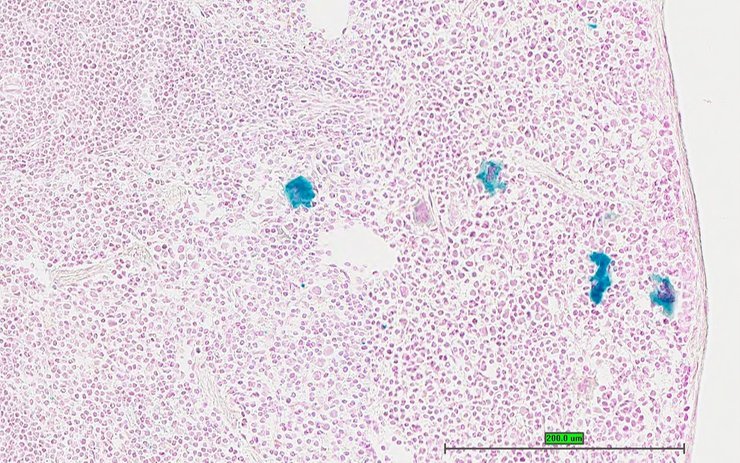

TS28: spleen Present UC Davis_1875950

Specimen UC Davis_1875951: postnatal adult; Ppbptm1.1(KOMP)Vlcg/Ppbp+ (more )

Structure Level Pattern Image Note

TS28: spleen Present UC Davis_1875951

TS28: spleen Present UC Davis_1875968

Specimen UC Davis_1875969: postnatal adult; Ppbptm1.1(KOMP)Vlcg/Ppbp+ (more )

TS28: spleen Present UC Davis_1875969